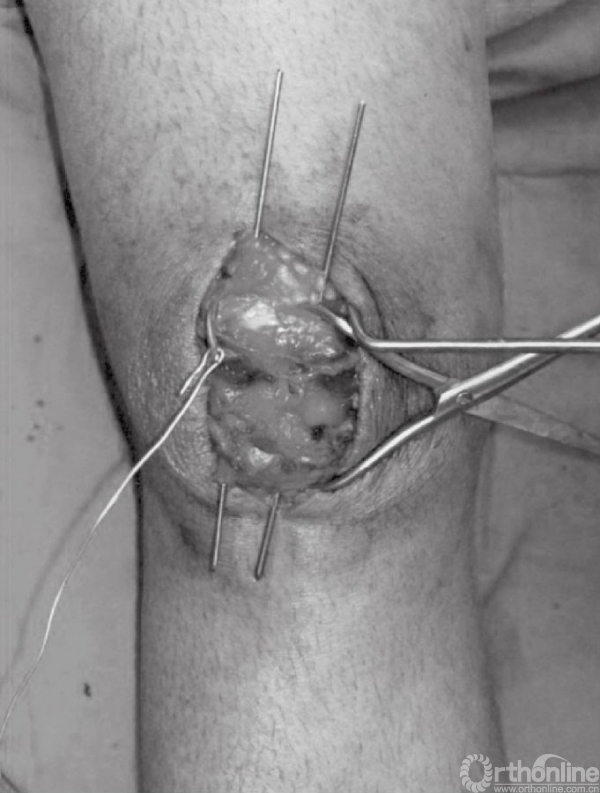

深层显露切口与皮肤切口方向一致。锐性分离深层筋膜,并牵开皮肤组织,进一步切开髌骨囊并清除血肿后骨折端即可显露(图4A和B)。此时,可见髌骨骨折以及撕裂的韧带。以生理盐水清洗血肿以及血凝块(图5)。撕裂的支持带可先辨识后,再进行修复。

图4 A和B切开髌骨关节囊,清除血肿后显露骨折块。图示髌骨横断型骨折,可见韧带撕裂

骨折末端应以小挂勺以及吸引器清除局部的血凝块。骨折端处的骨膜以及韧带应分离至骨折线周围2~3cm处,以免影响骨折复位。但应注意,不要清除髌骨周围过多的软组织,因为常有骨折块包含其中。

应仔细探查关节,以辨识游离骨块以及关节面损伤(图6)。此时,可对骨折进行复位,并以复位钳进行临时固定。检查骨折复位情况以及关节稳定性,关节内骨块的解剖复位是非常重要的。术中复位困难,可能是因为小骨块或者软组织嵌于骨折端。

图6 应仔细探查关节以辨识游离骨块以及关节面损伤